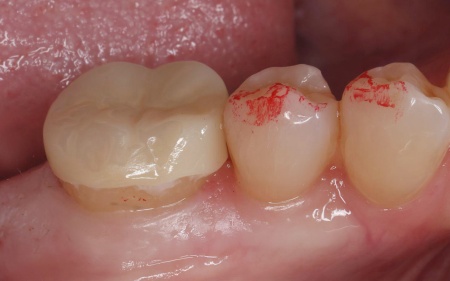

| 行ったご提案・治療内容 | 患者様は「周囲の歯になじむ自然な見た目で、長く安心して使える治療をしたい」と希望されていたため、通常の詰め物よりも広い範囲を覆う「オンレー」という修復方法を提案し、同意いただきました。

オンレーは、歯全体を覆う被せ物と比べると歯を削る量を抑えられるため、健康な歯をできるだけ残しながら、歯の強度を高めることが可能です。ただし、歯の状態によっては適応できない場合もあります。 まず、すでに装着されていた金属の詰め物を除去し、歯の状態を慎重に確認します。 次に、採取した歯型をもとにオンレーを作製します。 最後に、完成したオンレーを専用の接着剤で装着し、見た目や噛み合わせに問題がないことを確認して、治療を終了しました。 患者様の上の歯の治療についてはこちら:https://dr-kaiya.com/blog/20260312-1/ |

治療後